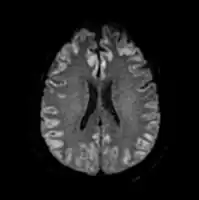

-

Acute severe hepatic encephalopathy -

Acute severe hepatic encephalopathy